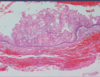

What is this infectious disease?

Oral Verruca Vulgaris

HPV 2,4,6

Also “finger‐like

projections”

remember it’s contagious